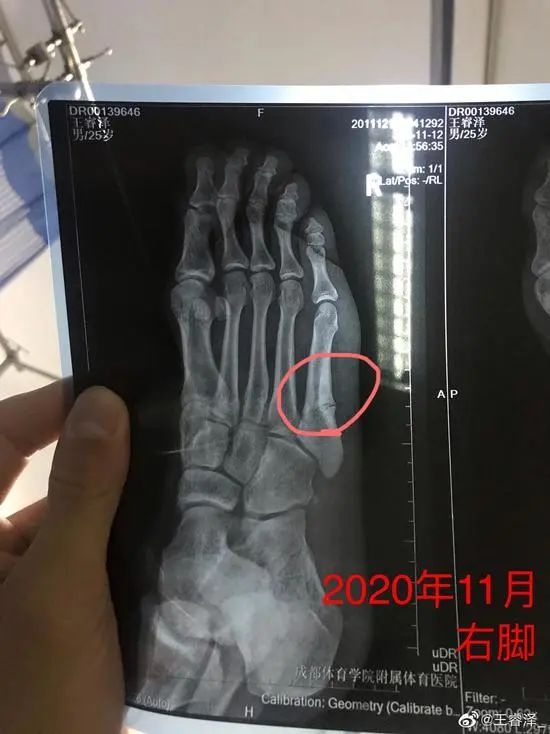

进入CBA以后,王睿泽左脚第五跖骨一直没事,倒是右脚开始隐隐作痛,他没当回事。或者换句话说,他也不敢把它当回事,“好不容易表现好一点了,好不容易感到教练在有意识地用你、关注你,我就怕一旦请假,会让教练觉得我‘坚持不了,吃不了苦’啥的。”作为边缘人的不安全感,让他必须抓住每一个细小的机会,所以,有点小伤小病他都坚持。直到再也坚持不了。

2020-2021赛季常规赛第9轮,青岛对阵同曦,王睿泽像往常一样积极地拼抢、跑位,那天他手风很顺,前3投全中得到8分。距离半场还剩2分47秒时,他试图绕过摩尔特里的掩护去追西热力江,右脚猛地一蹬地,当时就摔在地上起不来了。

王睿泽右脚骨折

右脚骨折

这一回,他在队医的建议下做了手术,也没再穿着保护靴到处走,而是在床上躺了2个月,稍微好点了就用个小车代步。他仍旧去健身房练习上肢力量,然后静静等待右脚的痊愈。就在他好不容易能自行走路,感觉重返赛场之日不远时,“腰不行了”。

事实上,在右脚受伤之前,他就有比较严重的腰伤,只是一直在坚持。而这一次,显然是坚持不住了,他骗得过自己的心,但骗不过身体。他坐在沙发上向我比划:“从左边屁股,一直到脚全麻了,脚趾抬不起来。”因为腰间盘突出,他甚至都顾不上刚刚长好的右脚,只能一边治腰一边等着右脚自行康复。